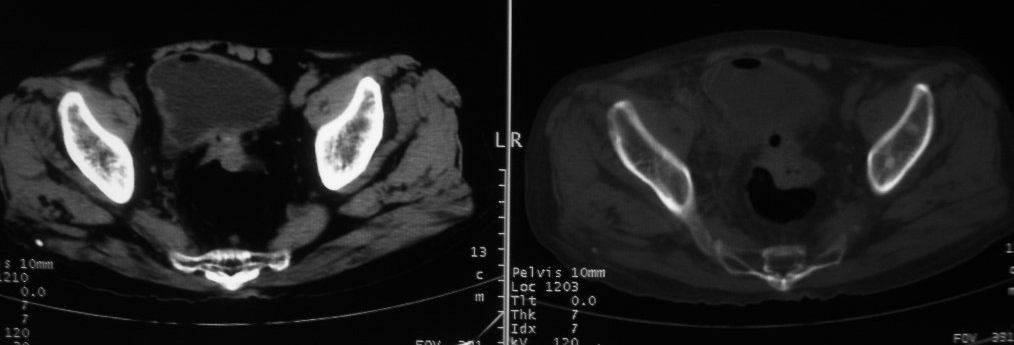

以下是引用深泽交通医院在2008-10-3 15:33:00的发言:[br]前列腺实性增大伴分叶状,与包膜间隙境界不清;椎体松质区间结节样密度影,考虑:前列腺癌,并椎体成骨性转移